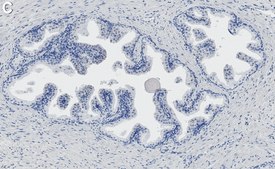

Immunohistochemistry (Paraffin) Analysis: A 1:1,000 dilution from a representative lot detected prostate specific antigen (PSA) in human prostate tissue sections.